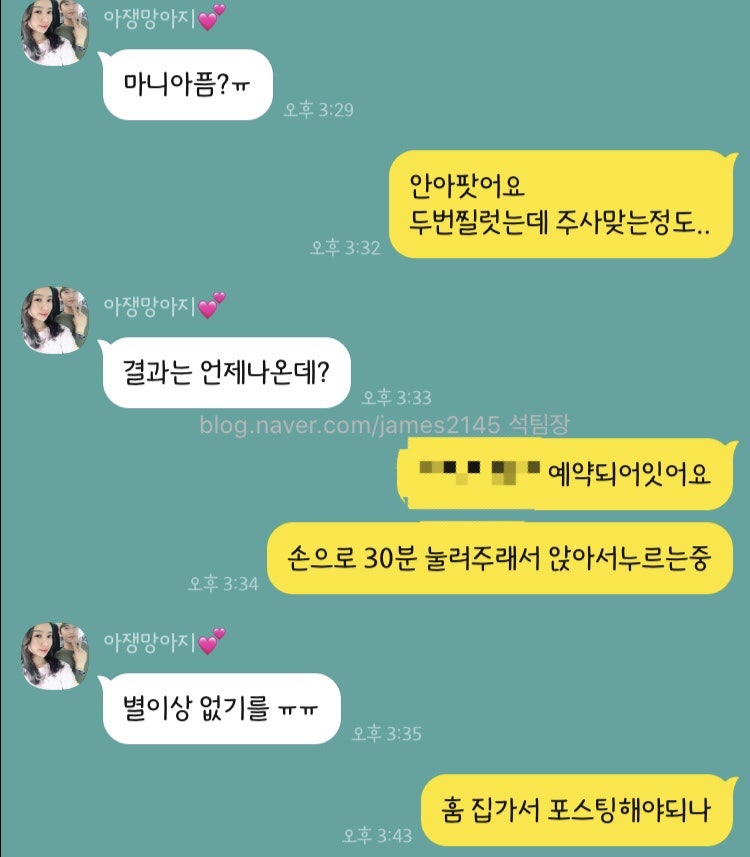

수치가 높게 나와서 정밀검사 진행했어요~

수치가 너무 높게 나왔기 때문에

너무 무서웠어요.

THS 정상 수치가 0.35~5.50인데,

29.6 나왔습니다.